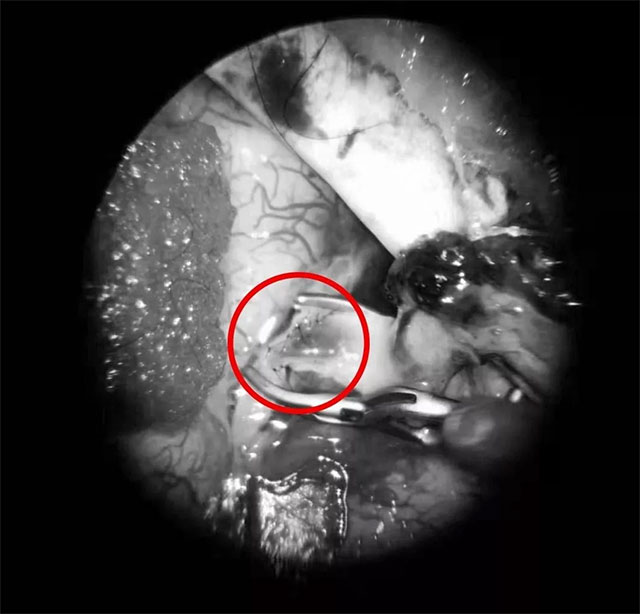

▲ 吻合口完美缝合

张琪博士在刘春医生和周林华医生协助下,在显微镜下将颅外颞浅动脉游离后引入颅内,与大脑中动脉分支行端侧吻合。由于吻合血管直径仅1mm左右,手术中在显微镜下使用仅有头发丝直径1/3的缝合线(10-0线)将吻合口缝合12针,才最终保证吻合口通畅并且无漏血。同时,进行硬脑膜翻转术。随后在复合手术室环境下,进行脑血管造影,显示搭桥血管血流通畅,颈动脉血流通畅,颈外动脉造影见颞浅动脉血流向受体动脉两端供血,搭桥手术成功,整个手术过程持续了5个多小时。